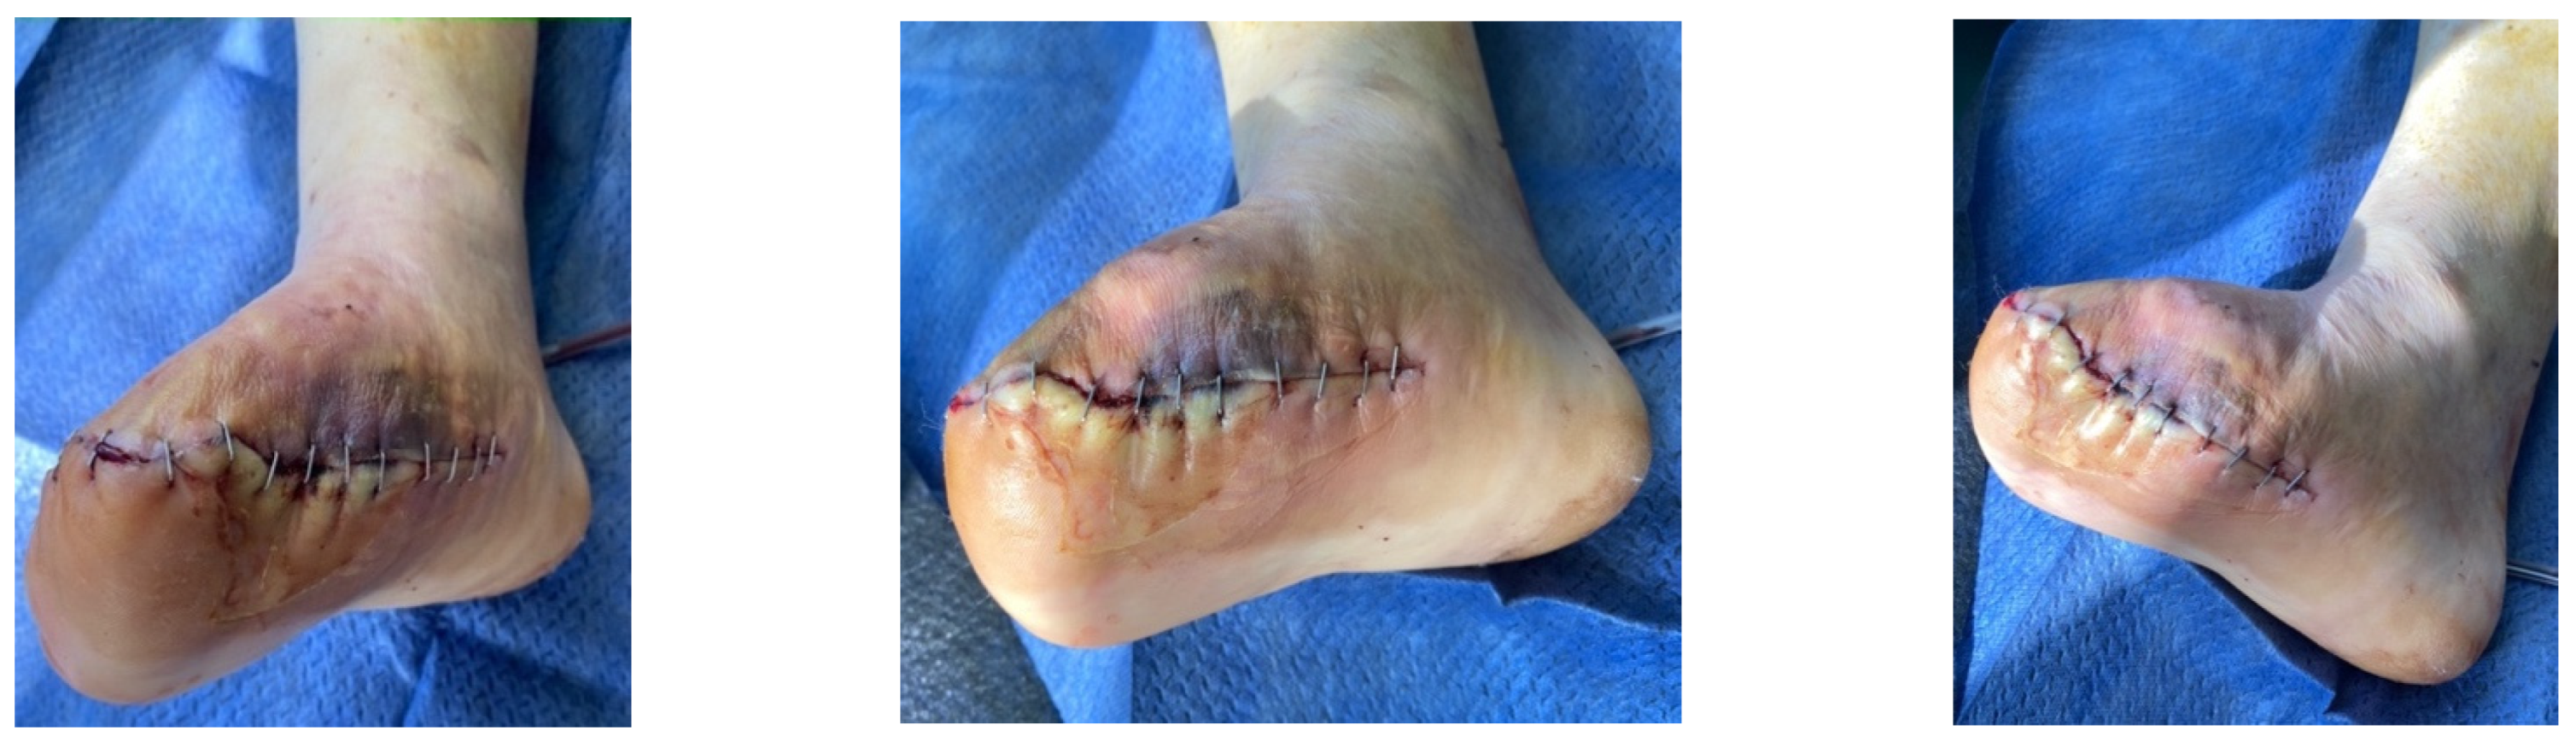

4.1. Case 1—Direct Revascularization-Minor Amputation